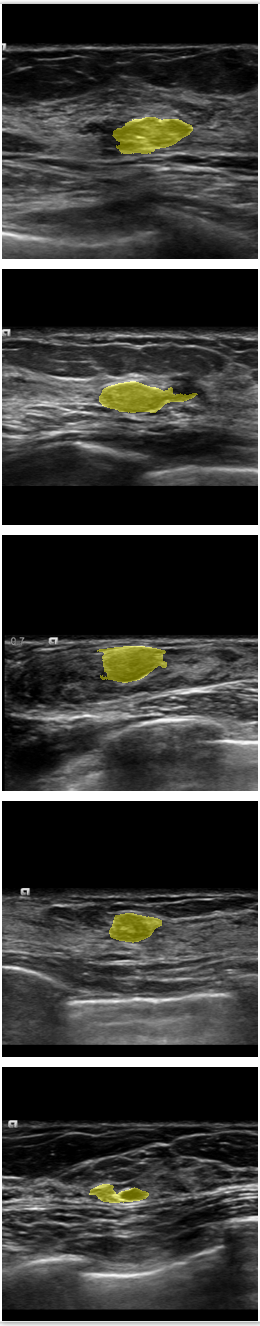

Refer to caption

Figure 6: Comparison of SPCGAN and other segmentation methods of benign lesions. (a) shows original image of benign lesions, (b) shows the manual annotation, (c) shows the result of SPCGAN ,(d), (e) and (f) show results from ResNet, Mask R-CNN and level set.

Fig.6 displays the segmentation results of our SPCGAN, FCN(ResNet), Mask R-CNN and the level set method from benign lesions. Compared with the FCN(ResNet) (d), Mask R-CNN (e) and the level set (f) method, the results of our SPCGAN (c) show good agreements with the manual contours of the lesions. The segmentations from SPCGAN are very close to manual segmentations.